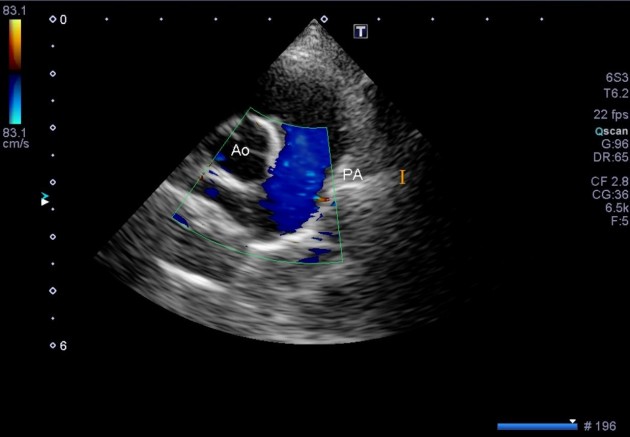

動脈管開存症は心臓の超音波(エコー)検査にて診断します。

この赤色の血液の流れが、動脈管の残存を表しています。

術後の超音波検査では血液の流れがすべて青色になり、血管が完全に閉鎖したことがわかります。